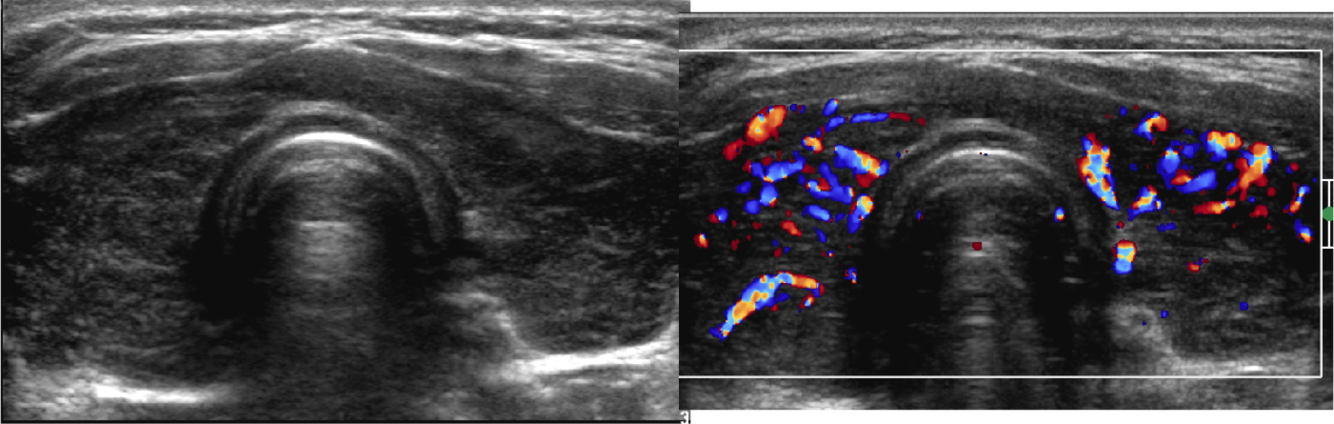

Cystic nodule

Dx?